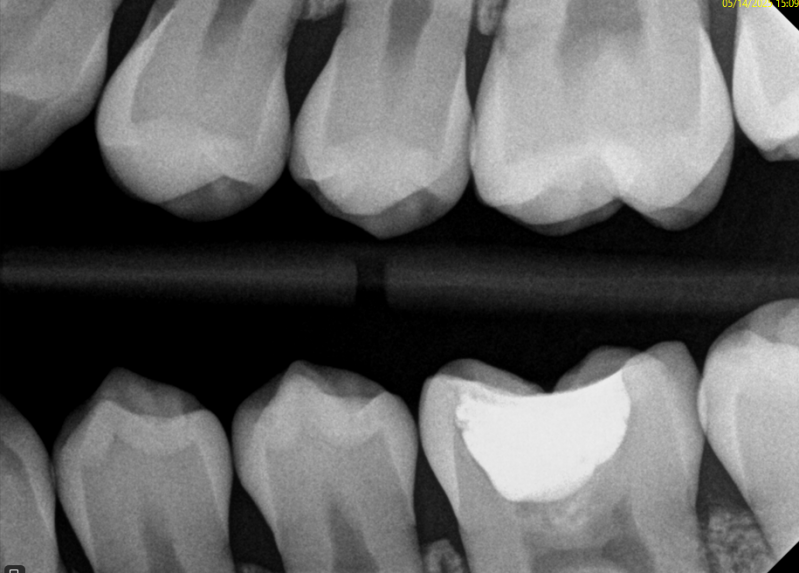

Case: RCT on Tooth #8,9

49-year-old male, chronic abdominal pain, history of small bowel obstruction ×4, gastritis (treated), colitis, on famotidine. NKDA.

Dx: Symptomatic irreversible pulpitis (#8, #9); normal apical tissues.

Tx: Root canal therapy due to pulpal exposure from severe occlusal wear.

Reflection

Restoring these teeth was questionable due to severe wear and limited vertical space. It was important to set expectations about the risk of not being able to place crowns afterward. The patient was still motivated to keep the teeth and chose RCT over extraction.